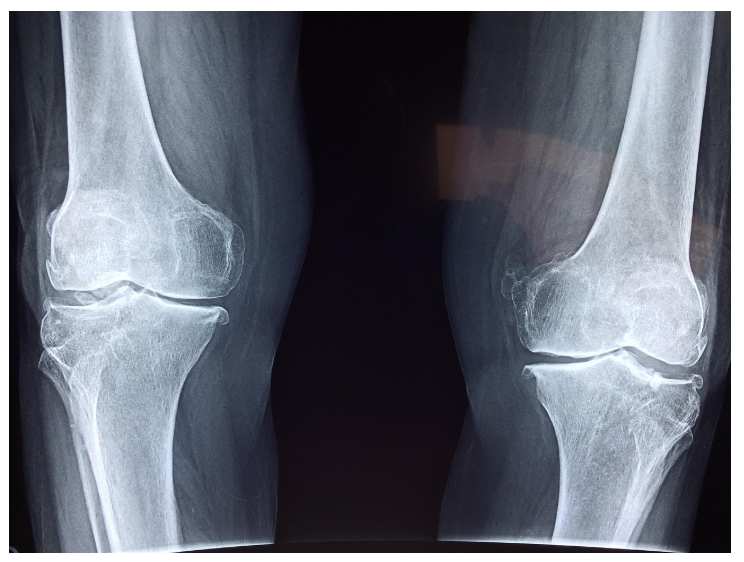

- X-ray(엑스레이):

연골은 투명 조직이기 때문에 X-ray로 직접 보이지 않지만, 연골 간격이 좁아졌는지를 통해 간접적으로 확인합니다. - MRI(자기공명영상):